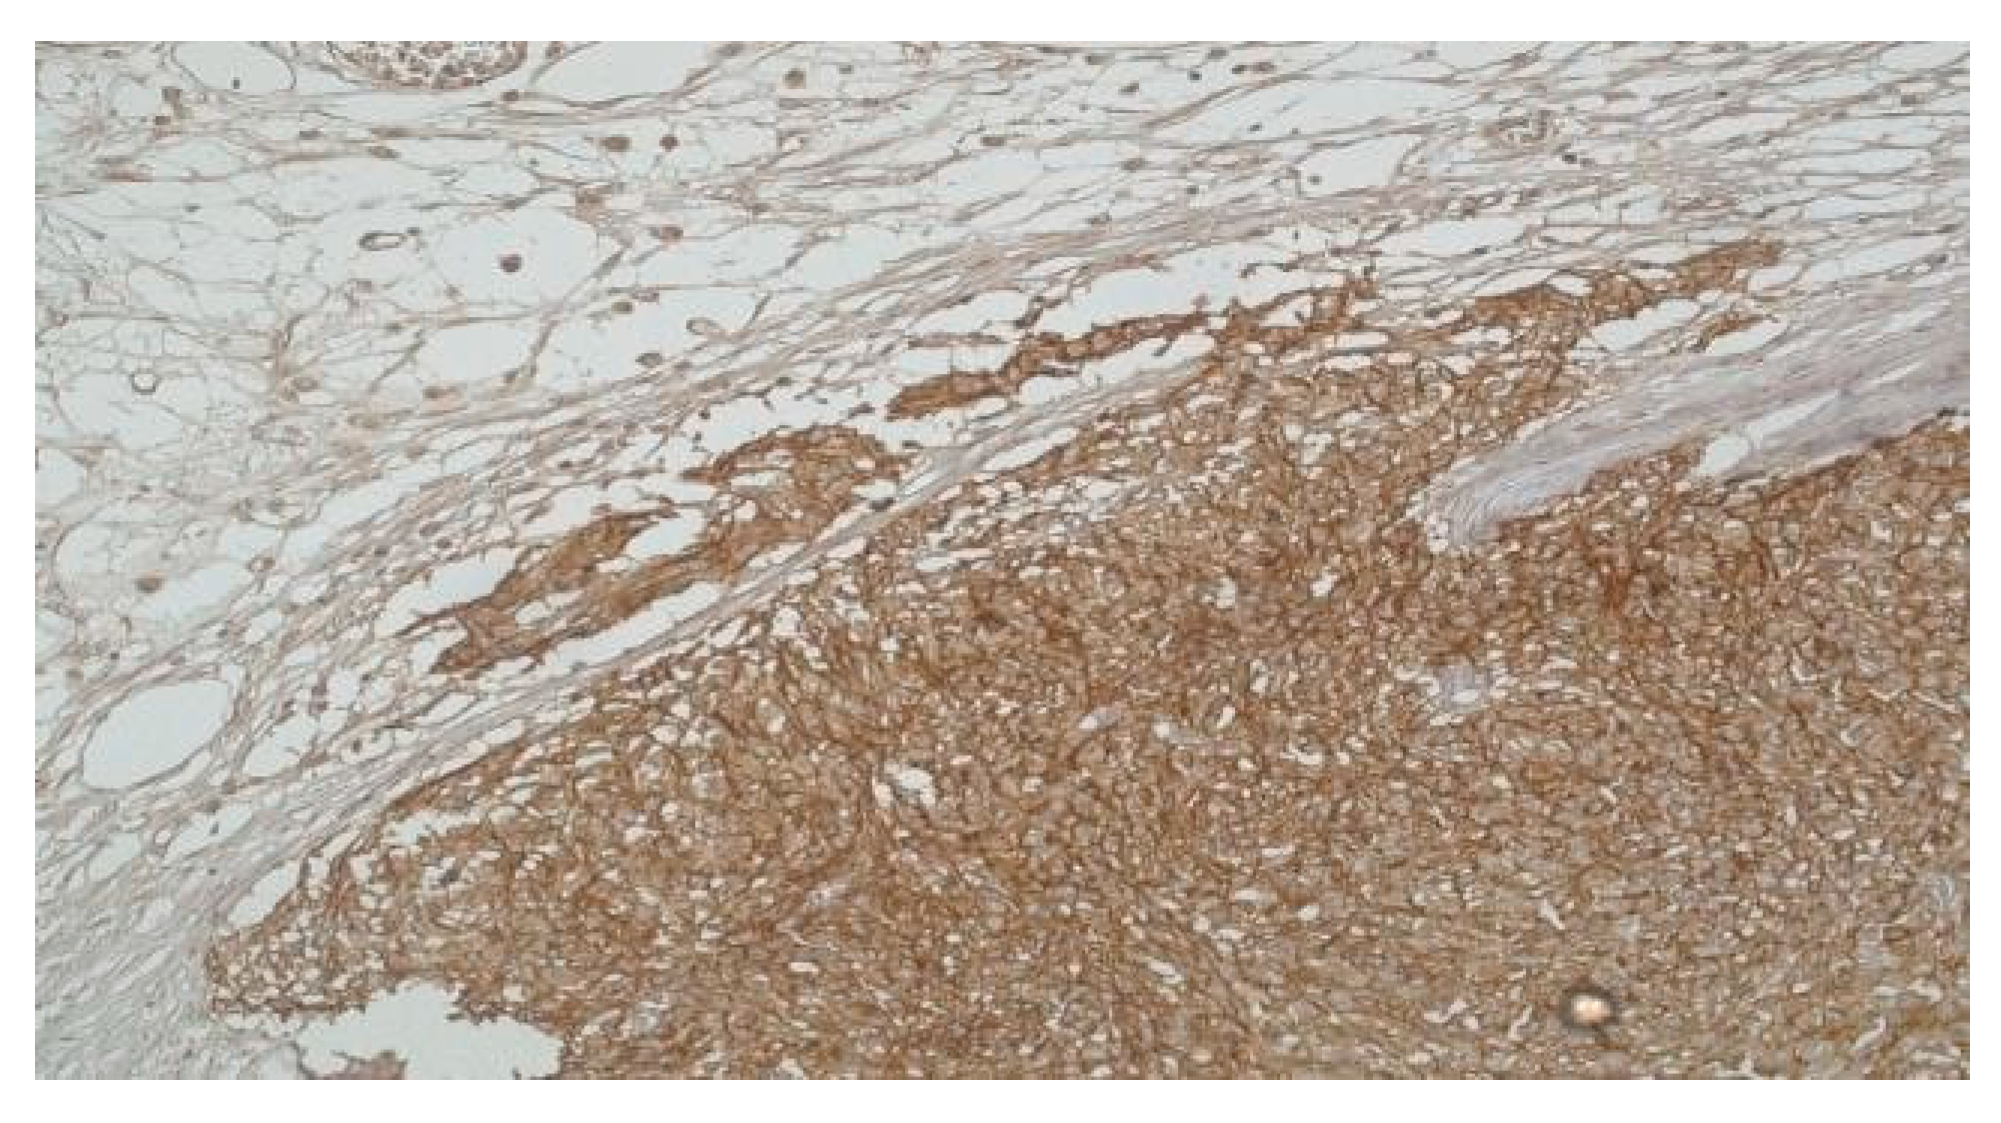

In the subset of GISTs classified as high-risk, a noteworthy majority—constituting 75% of cases (3 patients)—exhibited a pronounced presence of ICCs accompanied by heightened CD117 expression. Interestingly, one patient within this high-risk category presented a unique profile, showcasing reduced expression of both ICCs and CD117. Furthermore, from the very low- risk group, 40% of patients (2 individuals) displayed unexpectedly high levels of both CD117 and ICCs.

A distinctive observation emerged, shedding light on the diversity within the high-risk and very low-risk groups. The remaining cases, categorized as very low-risk and low- risk (6 patients), consistently demonstrated diminished levels of both ICCs and CD117 (Figure 2).

These nuanced findings suggest a potential correlation between the abundance of ICCs and CD117 expression and the overall risk classification of GISTs. This underscores the intricate interplay of these immunohistochemical markers in delineating the tumor's risk profile.

Figure 2. High-risk gastric GIST, Fusiform Pattern (CD 117 x 40) and High-risk gastric GIST -Fusiform Pattern (H and E x 40).